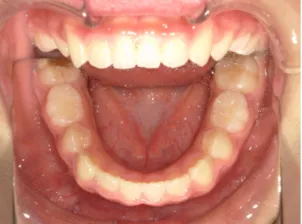

小1女子、生え変わってきても受け口なので治したい女子

治療前①小1(7y2m):初診

*上顎前歯後方傾斜、上下唇の突出、口唇閉鎖不全傾向、コンケーブなし

| カウンセリング・診断結果 | 骨格的に下顎前方位で下顎骨も大きいタイプで、上の前歯が後ろに傾斜している受け口です。 顔立ちは上下唇が突出していて口唇閉鎖不全傾向がありますが、コンケーブにはなっていません(写真①)。 機能的に低位舌があり、今後受け口を助長する可能性があります。 受け口は、上顎骨の骨格的な前方向の成長を阻害し下顎が前へ強く成長していくため、骨格的な受け口が悪化し永久歯の咬合治療が難しくなり、症例によっては外科的な治療が必要になることがあるため早期に改善し骨格的な悪化を予防する説明をしました。 |